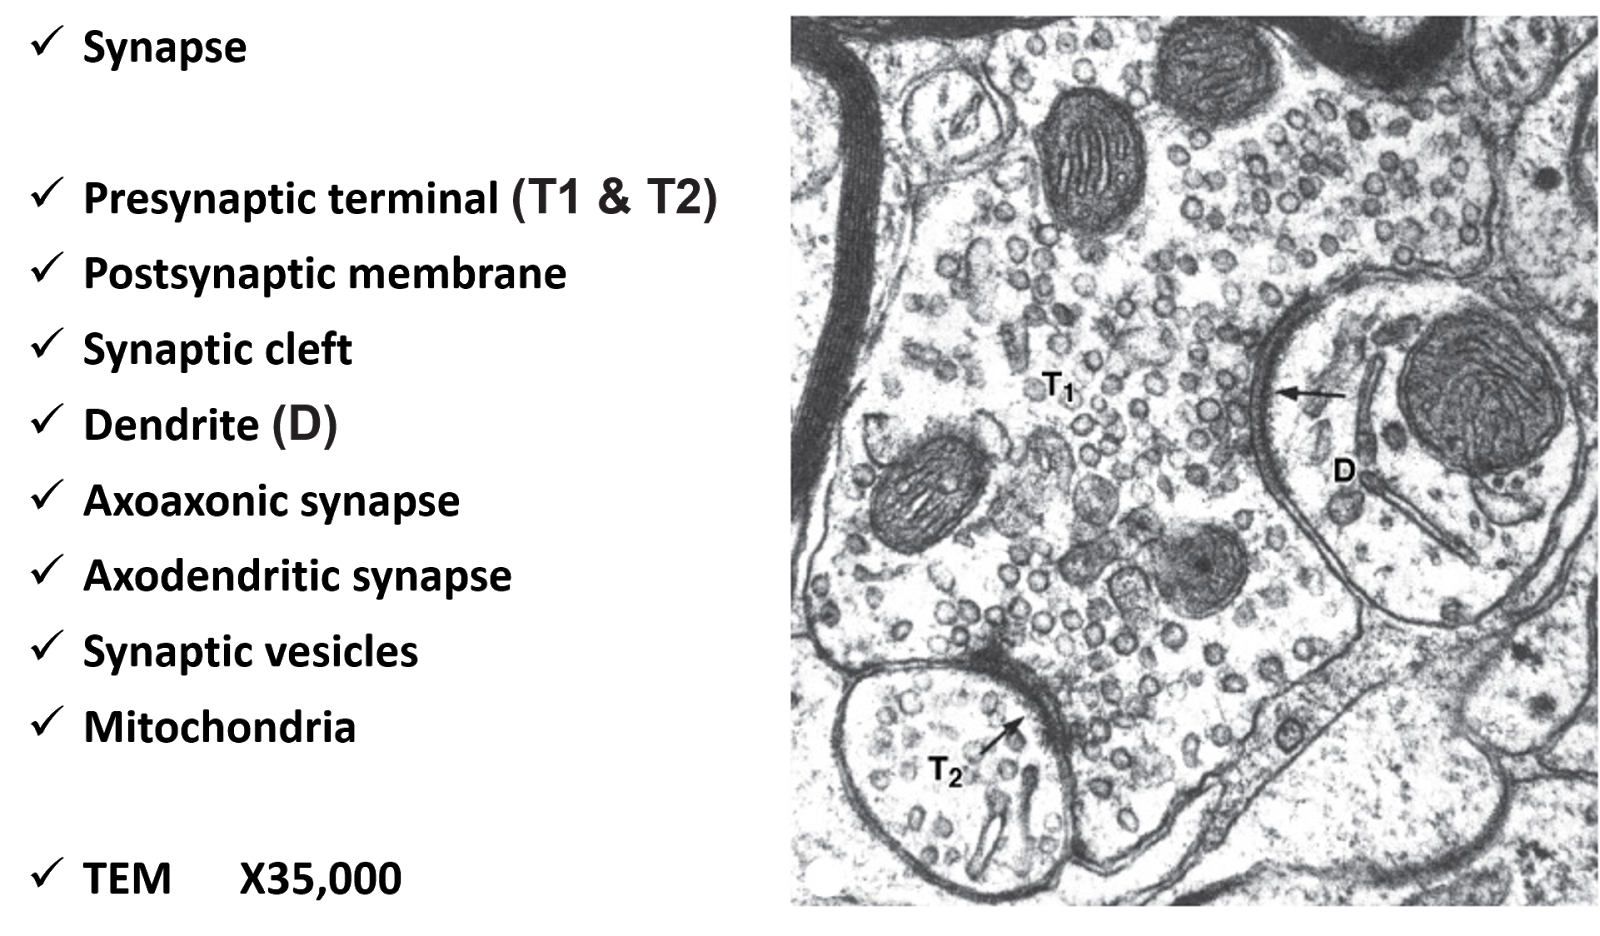

Аксо соматические

Аксо соматические 108 фотографий